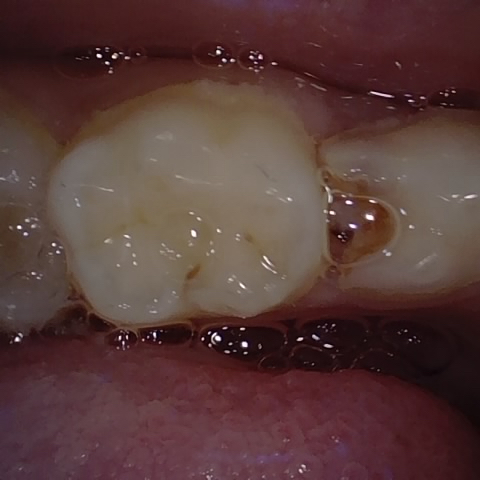

Annotated as "Good"